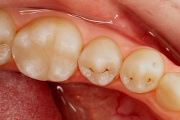

Ravijärgne seis. Jäävhammas on täielikult lõikunud.

) Röntgenülesvõte. Ülemise esimese jäävmolaari lõikumine on takistatud 2. piimamolaari tõttu